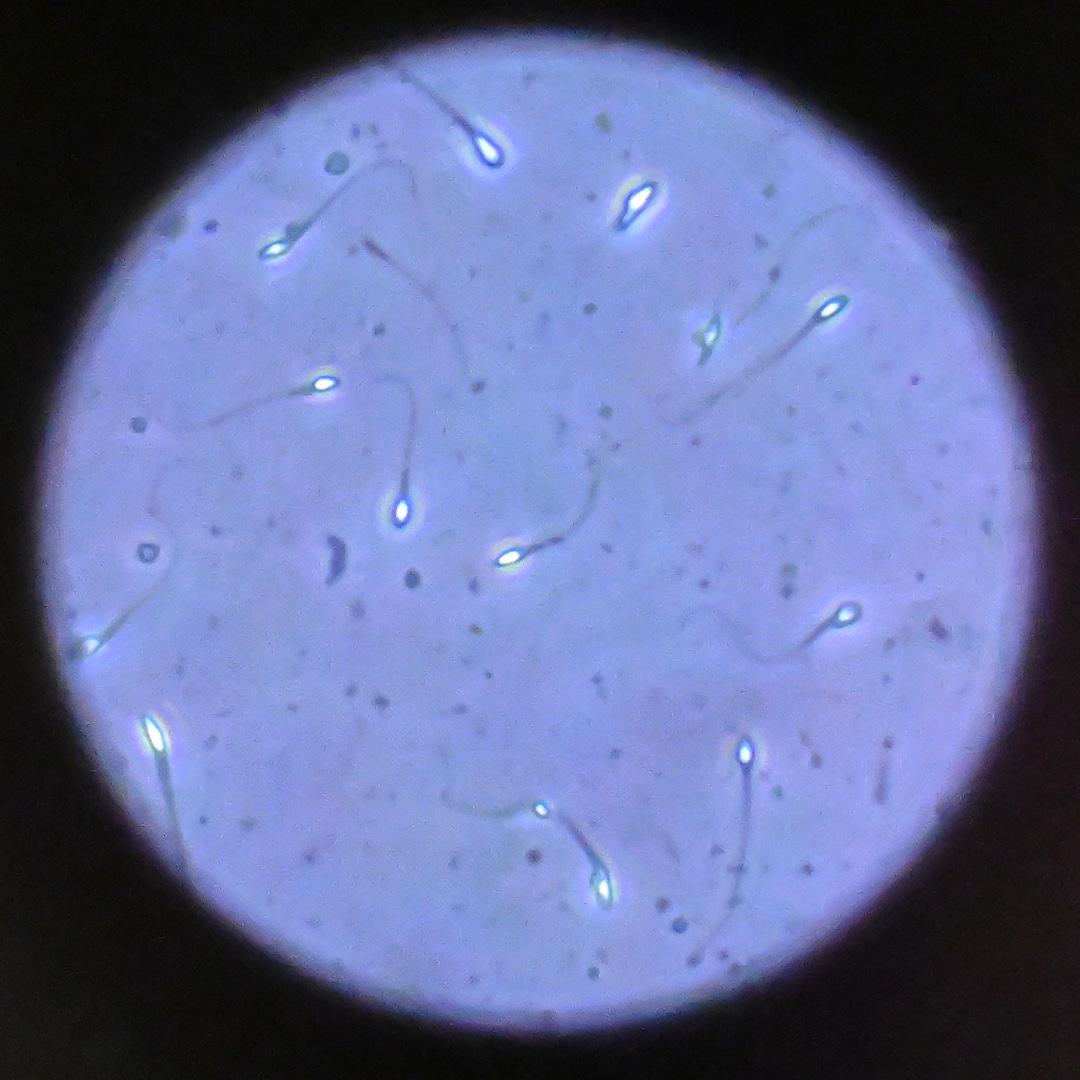

Sperm Donor With Rare Mutation Linked to Cancer Sparks Debate

A sperm donor with a rare genetic mutation linked to cancer is sparking debate about regulation of the practice.

In the years between 2008 and 2015, sperm from the same donor was used to conceive...

A sperm donor with a rare genetic mutation linked to cancer is sparking debate about regulation of the practice.